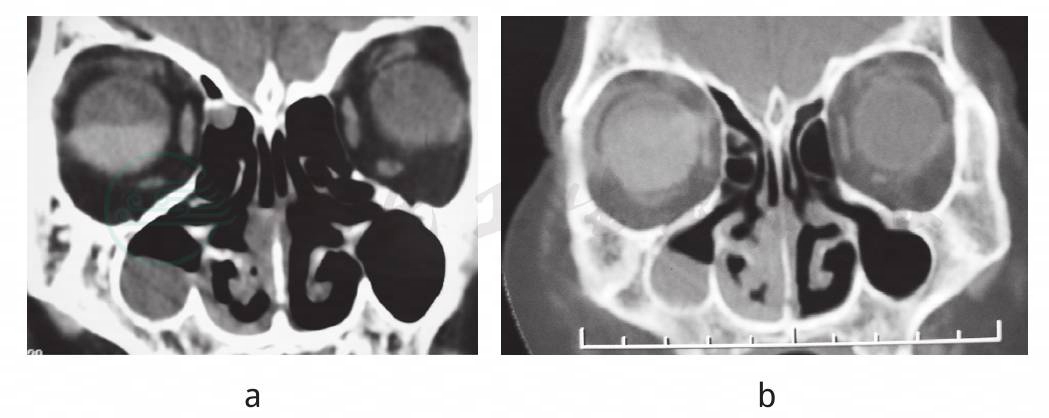

a.3年前鼻窦CT示右上颌窦内软组织密度影,右鼻腔及鼻中隔右侧黏膜增厚;右眼视网膜脱离;b.3年后鼻窦CT示右上颌窦软组织密度增多,视网膜脱离消失

鼻科检查:双中鼻道见脓性分泌物,右侧为重,右上颌窦区压痛。右外耳道充血,少许分泌物。鼻窦CT示双筛窦、右上颌窦及蝶窦内见软组织影(图1b)、双侧鼻中下鼻道软组织影,右侧为重;右眼球密度不均;听力测定发现双耳听力下降;颞骨CT示乳突窦、乳突蜂房及中耳腔可见密度增高影,部分层面可见液气平。诊断为急性鼻窦炎、右外耳道炎、右侧中耳乳突炎,予以抗生素治疗无效。